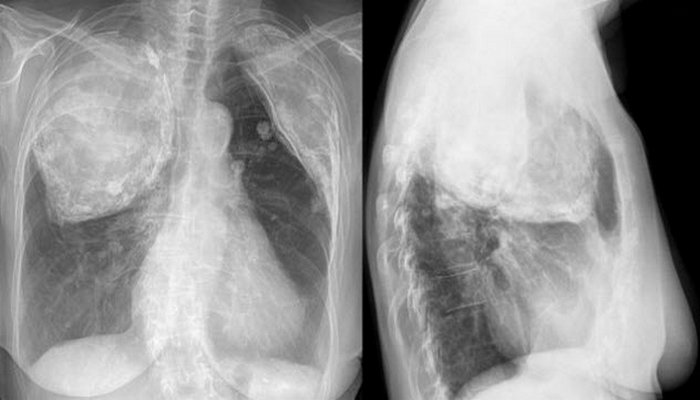

8. Пломбаж

Жуткая медицина: пломбаж.

С 1930-х по 1950-е годы туберкулез был одной из основных причин смерти. В то время антибиотики были редкими, и никаких лекарств для лечения туберкулеза не было. Тем не менее, существовала медицинская процедура под названием «пломбаж», которая заключалась в заполнении плевральной полости пациента (область легких за грудной клеткой) случайными материалами, такими как минеральное масло, шарики Люцита, марля, парафин или воск, каучук и животный жир.

Существует даже опубликованное исследование операций пломбажа, проведенных над детьми, в которых в качестве наполнителей использовались стерилизованные шарики от пинг-понга. Эта процедура заставляла легкое коллапсировать и более не функционировать. Согласно теории, если больное легкое коллапсировало, оно со временем исцелялось.

Операция часто позволяла пациенту прожить дольше, поскольку приводила к краткосрочному улучшению. Однако спустя десятилетия были замечены многие осложнения, часто от инфекции, кровоизлияния или движения в грудной клетке инородного наполнителя. К счастью, после появления современных антибиотиков для лечения туберкулеза в 1950-х годах операции пломбажа прекратили делать.